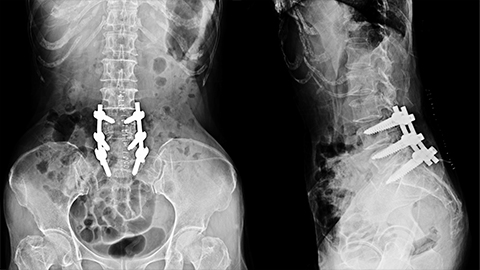

X-ray of spine showing a lumbar fusion

A client has chronic low-back pain, headaches, migraines, and a history of some serious surgeries. We take a close look at one of them: spinal fusion at L4-L5. What is this massage therapist doing now? What might he do in the future? It turns out there are a lot of options!